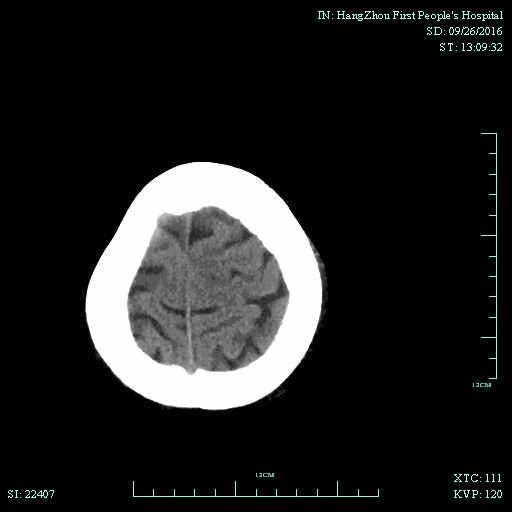

辅助检查:血常规、生化、凝血功能未见明显异常,心电图:心房颤动,ST-T改变;头颅CT平扫未见明显出血。

▼术前头颅CT平扫:

▼术后头颅CT复查:未见明显出血,左侧脑室旁可见少许低密度病灶。